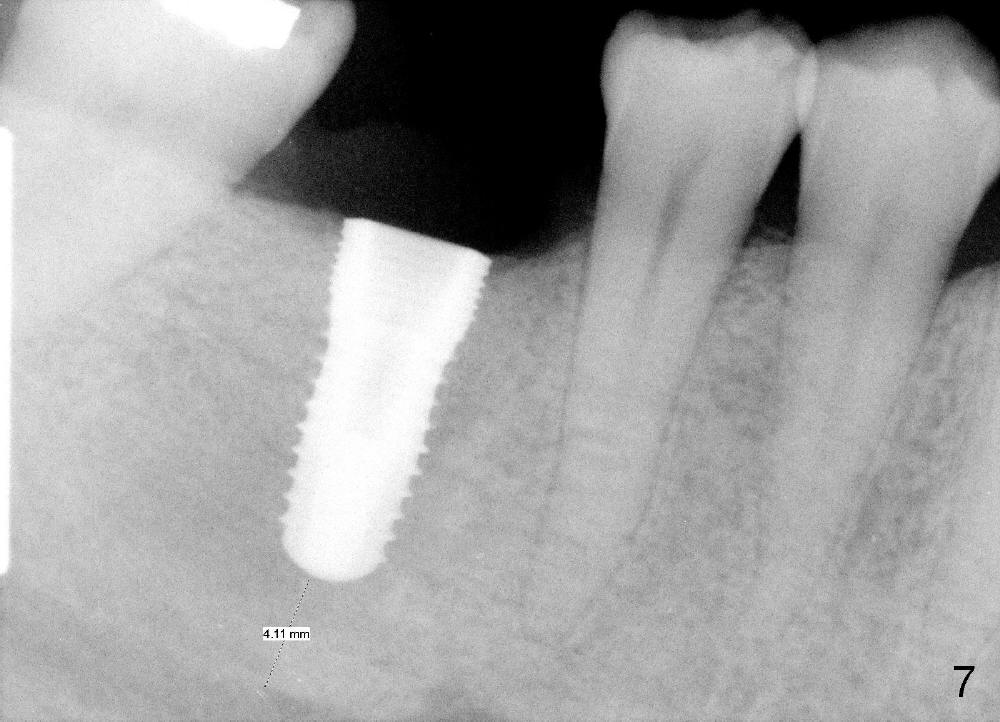

A 5.3x12 mm implant is placed at the crest level (Fig.7,8). The harvested bone from reamers' osteotomy (Fig.9) is placed buccal and lingual to the implant, where there is a half or 1 exposed microthread. The bone graft is then covered by collagen membrane. The periosteum is underscored; the flaps are sutured. The wound is covered by perio dressing. The patient continues postop oral antibiotic.